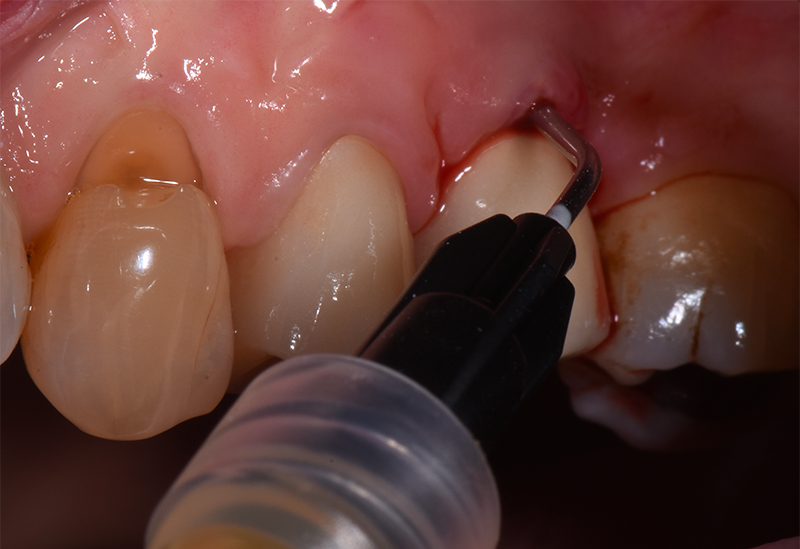

Nell'ultimo anno le è stata riscontrata complicanza a carico dei tessuti peri-implantari di elemento zona 25. L'esame visivo e lo status fotografico (Figs. 1-2) evidenziano un’alterazione dello stato dei tessuti molli peri-implantari, che guida il clinico verso un’indagine più approfondita tramite acquisizione RX. Si esegue perciò esame radiografico del sito coinvolto (Fig. 3), da cui risulta un’importante riassorbimento osseo a carico dell’impianto. Si procede con sondaggio peri-implantare profondo, con la finalità di definire estensione e forma del difetto (Fig. 4) e, associandolo all’esame radiografico, di eseguire la conta delle spire implantari esposte. Tale manovra verrà effettuata con l’impiego di anestetico da irrigazione, data la nota dolorolabilità in peri-implantite, in quanto tale patologia determina la perdita di barriere connettivali e pertanto la penetrazione in osso durante il sondaggio.

Sondaggio perimplantare profondo

Fig. 4 - Sondaggio peri-implantare profondo.